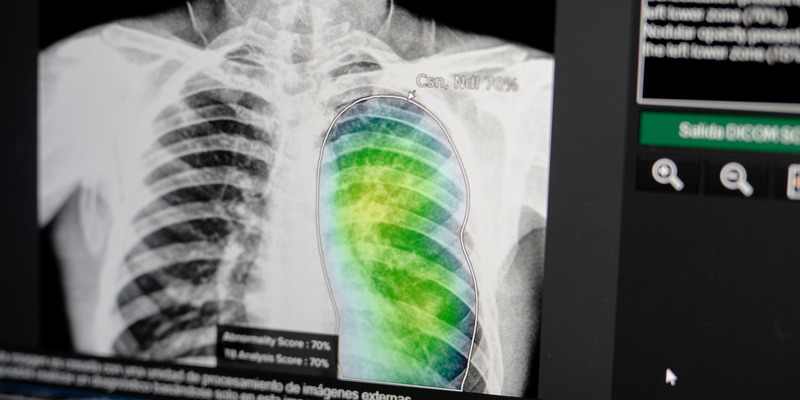

Chest Camps in Pakistan Bring TB Services to the People